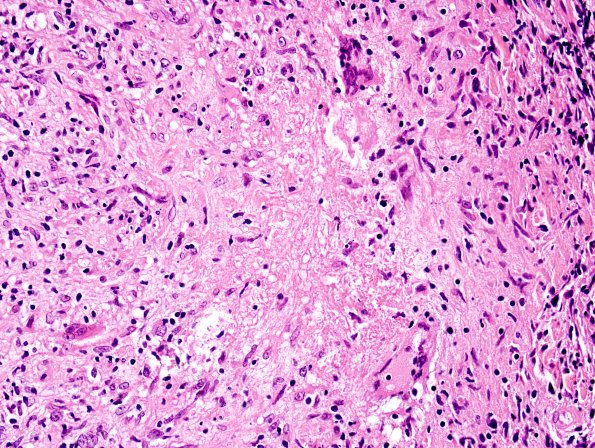

5A10 Leprosy, tuberculoid (Case 5) H&E 9

Another granuloma with a population of multinucleated giant cells. (H&E)